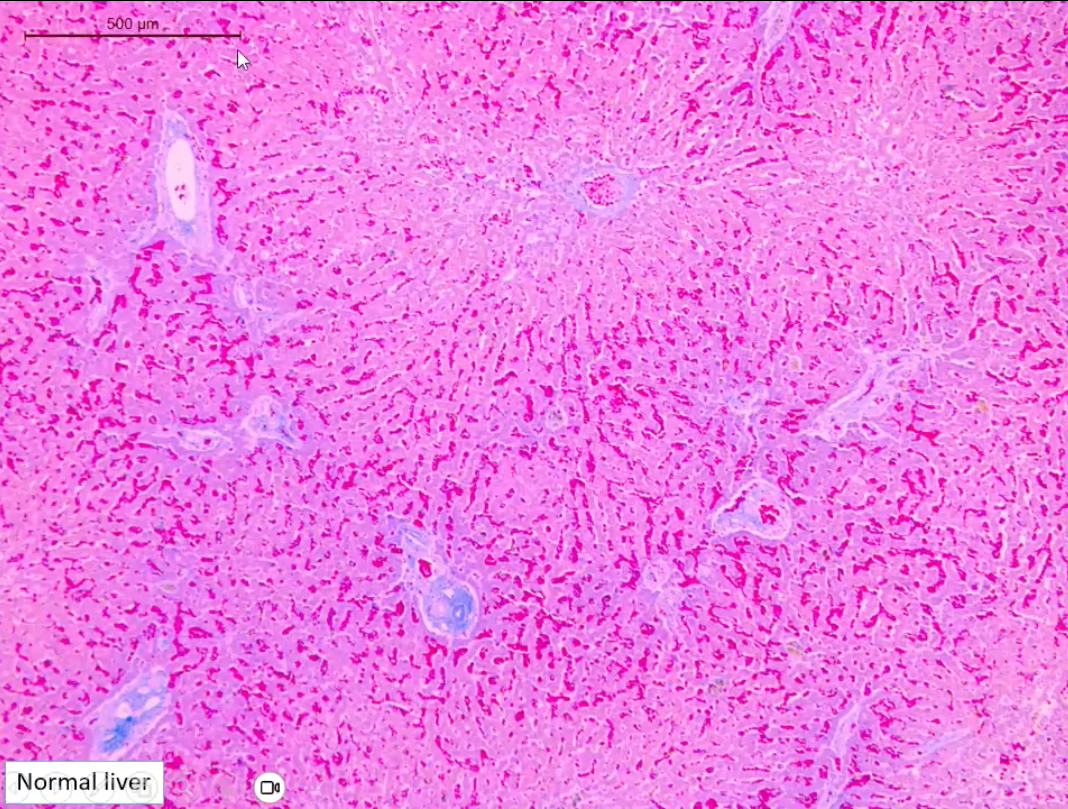

how do we know this is the liver?

A

lobules

portal area